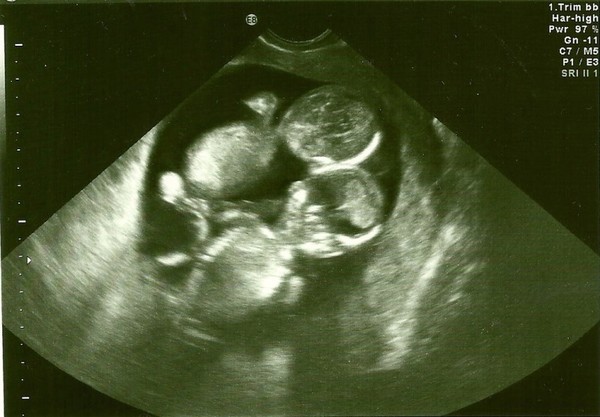

A few weeks that followed the discovery, the couple decided to go for their first ultrasound, and the doctor joked: “Let us examine the heartbeat to find out if there is more than one baby in there!” The only thing that he didn’t know was that his joke would turn out to be the reality.

Just a few minutes had passed before the doctor lifted his hand of two fingers pointing up while the rest of the fingers folded.

“Two babies are in there!” the doctor said affirmatively. Everyone was happy for the new revelation including the couple themselves.

The ultrasound results indicated that the two babies had first separated at around 8 to 13 days following the implantation, which implied that there was no protective membrane separating the twins. That sounded strange to many who are not conversant with such terms. It even confused many people and if you are feeling the same, don’t worry, you are not alone.

The twins, who were discovered to be all girls, were monoamniotic twins. That means that apart from being identical, they share the same umbilical cord and an inner fetal sack. What close association these two souls had? If they would survive, then we are expecting to see inseparable duo!